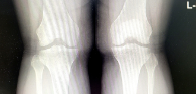

슬개골은 대퇴골과 종아리뼈 사이에 위치하며 대퇴골과 함께 무릎 관절을 형성하는 삼각형 모양의 큰 뼈입니다. 슬개골은 대퇴골에 부착된 근육과 인대에 의해 제자리에 고정되며 무릎 관절의 움직임에 중요한 역할을 합니다. 슬개골에 이상이 생기면 무릎 통증, 부종, 무릎 갈라짐 등의 증상이 나타날 수 있다.

슬개골 연골 연화증은 슬개골과 대퇴골 사이에 위치한 슬개골 연골이 퇴화, 손상 또는 연화되는 상태입니다. 주로 중년 이상의 여성에게 발생하며 골다공증, 슬개골의 비정상적인 움직임, 유전적 요인에 의해 발생합니다. 증상으로는 슬개골 통증, 불안정성 및 퇴행성 변화가 있습니다. 진단은 X-ray, MRI, 초음파 등으로 확인할 수 있으며 치료는 보존적 치료(약물치료, 근육강화운동 등)와 수술적 치료(슬개골 전진술, 전후방 창상수술 등)가 있다. 빠른 진단과 치료가 필요하며 방치할 경우 슬개골 퇴행성관절염, 연골파괴 등 심각한 합병증이 발생할 수 있다.